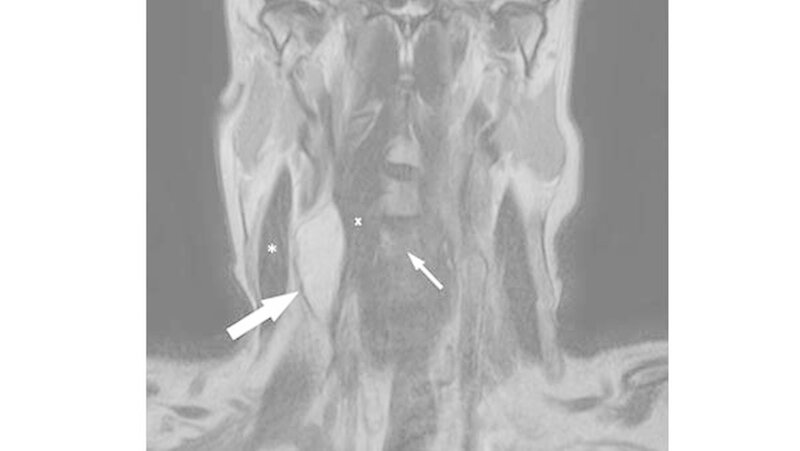

Im MRT zeigte sich korrelierend zum Tastbefund eine spindelförmige Raumforderung mit den Ausmaßen von 5x2x2cm paravertebral auf Höhe HWK 3 bis HWK 6 (Abbildung 1). Der Befund verdrängte sowohl den prävertebrale M. longus colli als auch die Arteria carotis nach ventral.

Die Vena jugularis interna war subtotal komprimiert. Kleinere Ausläufer der Raumforderung lagen unmittelbar lateral des Neuroforamens der Radix C5, unterhalb des HWK 4 und reichten bis auf 3mm an die Arteria vertebralis heran (Abbildung 2). Ein infiltratives Wachstum war radiologisch nicht nachweisbar.